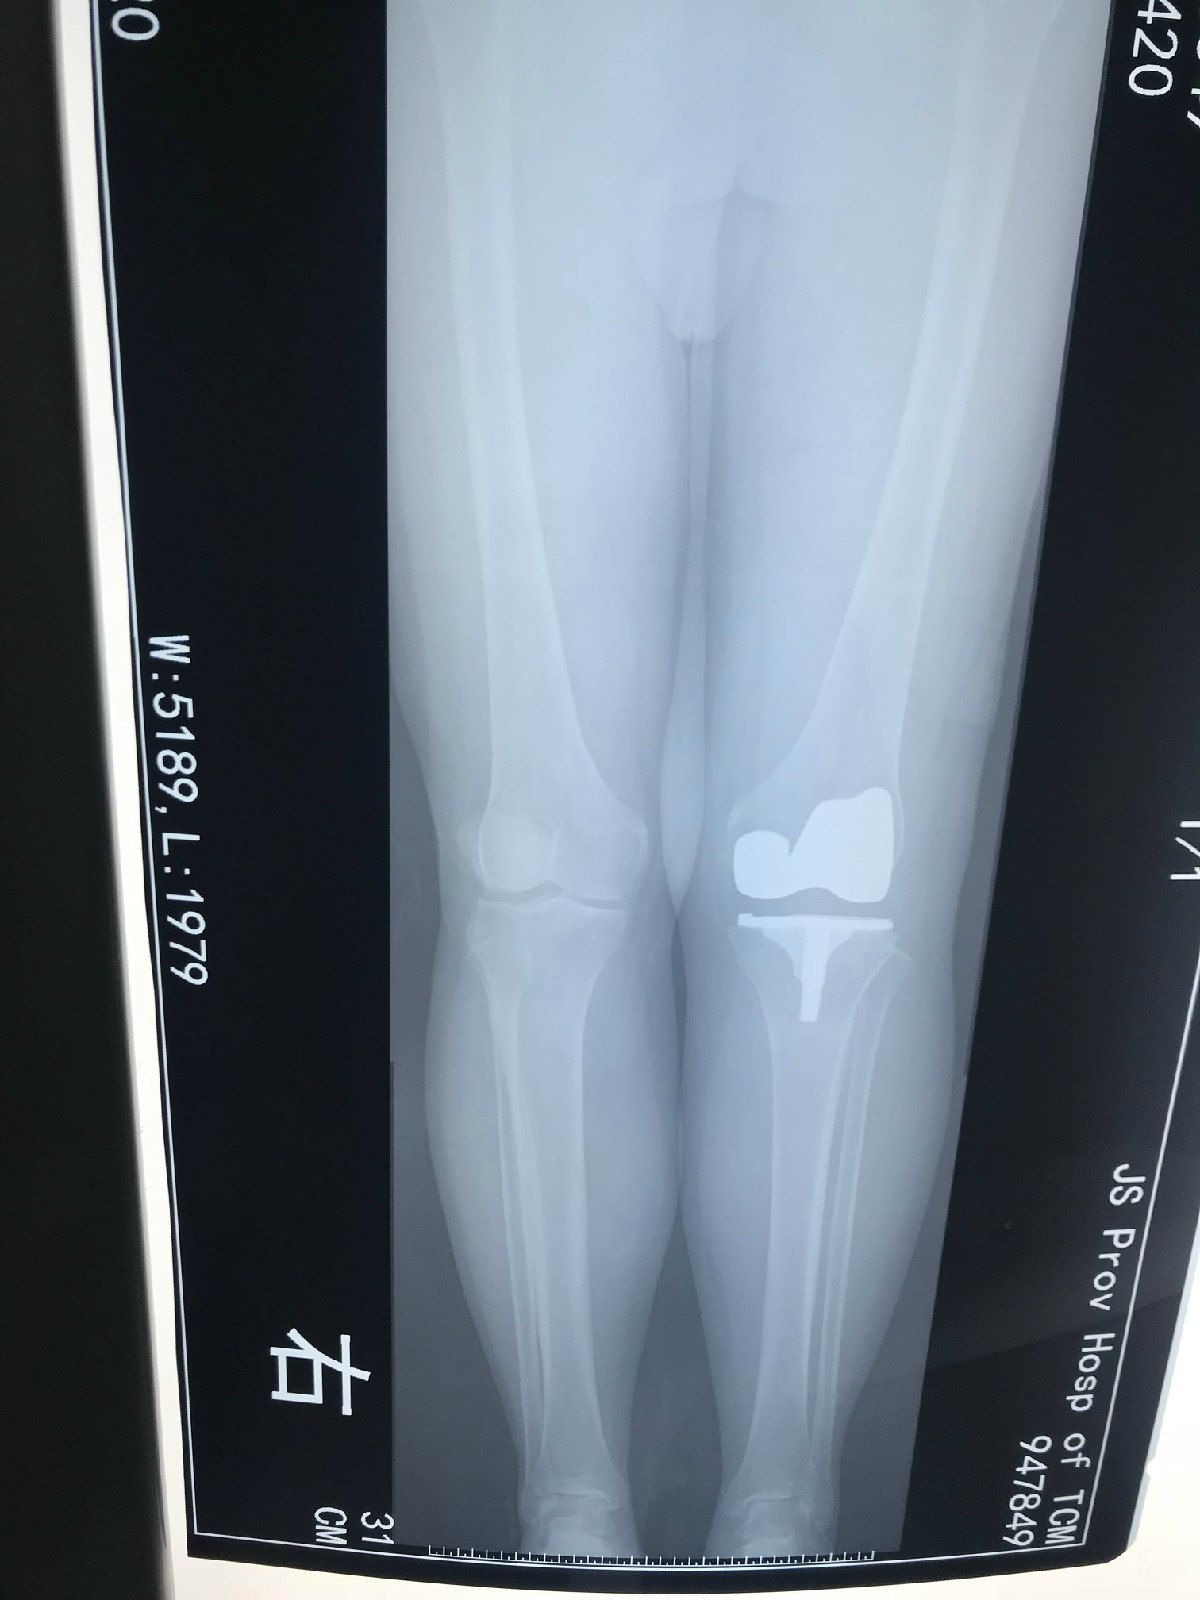

43岁女性重度外翻膝疼痛行走困难双侧截骨矫形术

外翻膝术前.png